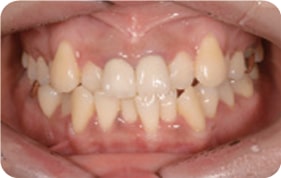

Case 3

2017. 10. 11

2017. 12. 26

2018. 02. 26